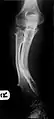

It is characterized by the growth of cartilage-capped benign bone tumours around areas of active bone growth, particularly the metaphysis of the long bones. Typically five or six exostoses are found in upper and lower limbs. Image depicts adult regrowth after knee replacement.

The diagnosis of HMO is based upon establishing an accurate correlation between the above-mentioned clinical features and the characteristic radiographic features. Family history can provide an important clue to the diagnosis. This is supplemented by testing for the two genes in which pathogenic variants are known to cause HMO namely EXT1 and EXT2. A combination of sequence analysis and deletion analysis of the entire coding regions of both EXT1 and EXT2 detects pathogenic variants in 70–95% of affected individuals.[3][4] The hallmark of radiographic diagnosis is the presence of osteochondromas at the metaphyseal ends of long bones in which the cortex and medulla of the osteochondroma represent a continuous extension of the host bone. This is readily demonstrable in radiographs of the knees.[3][1]